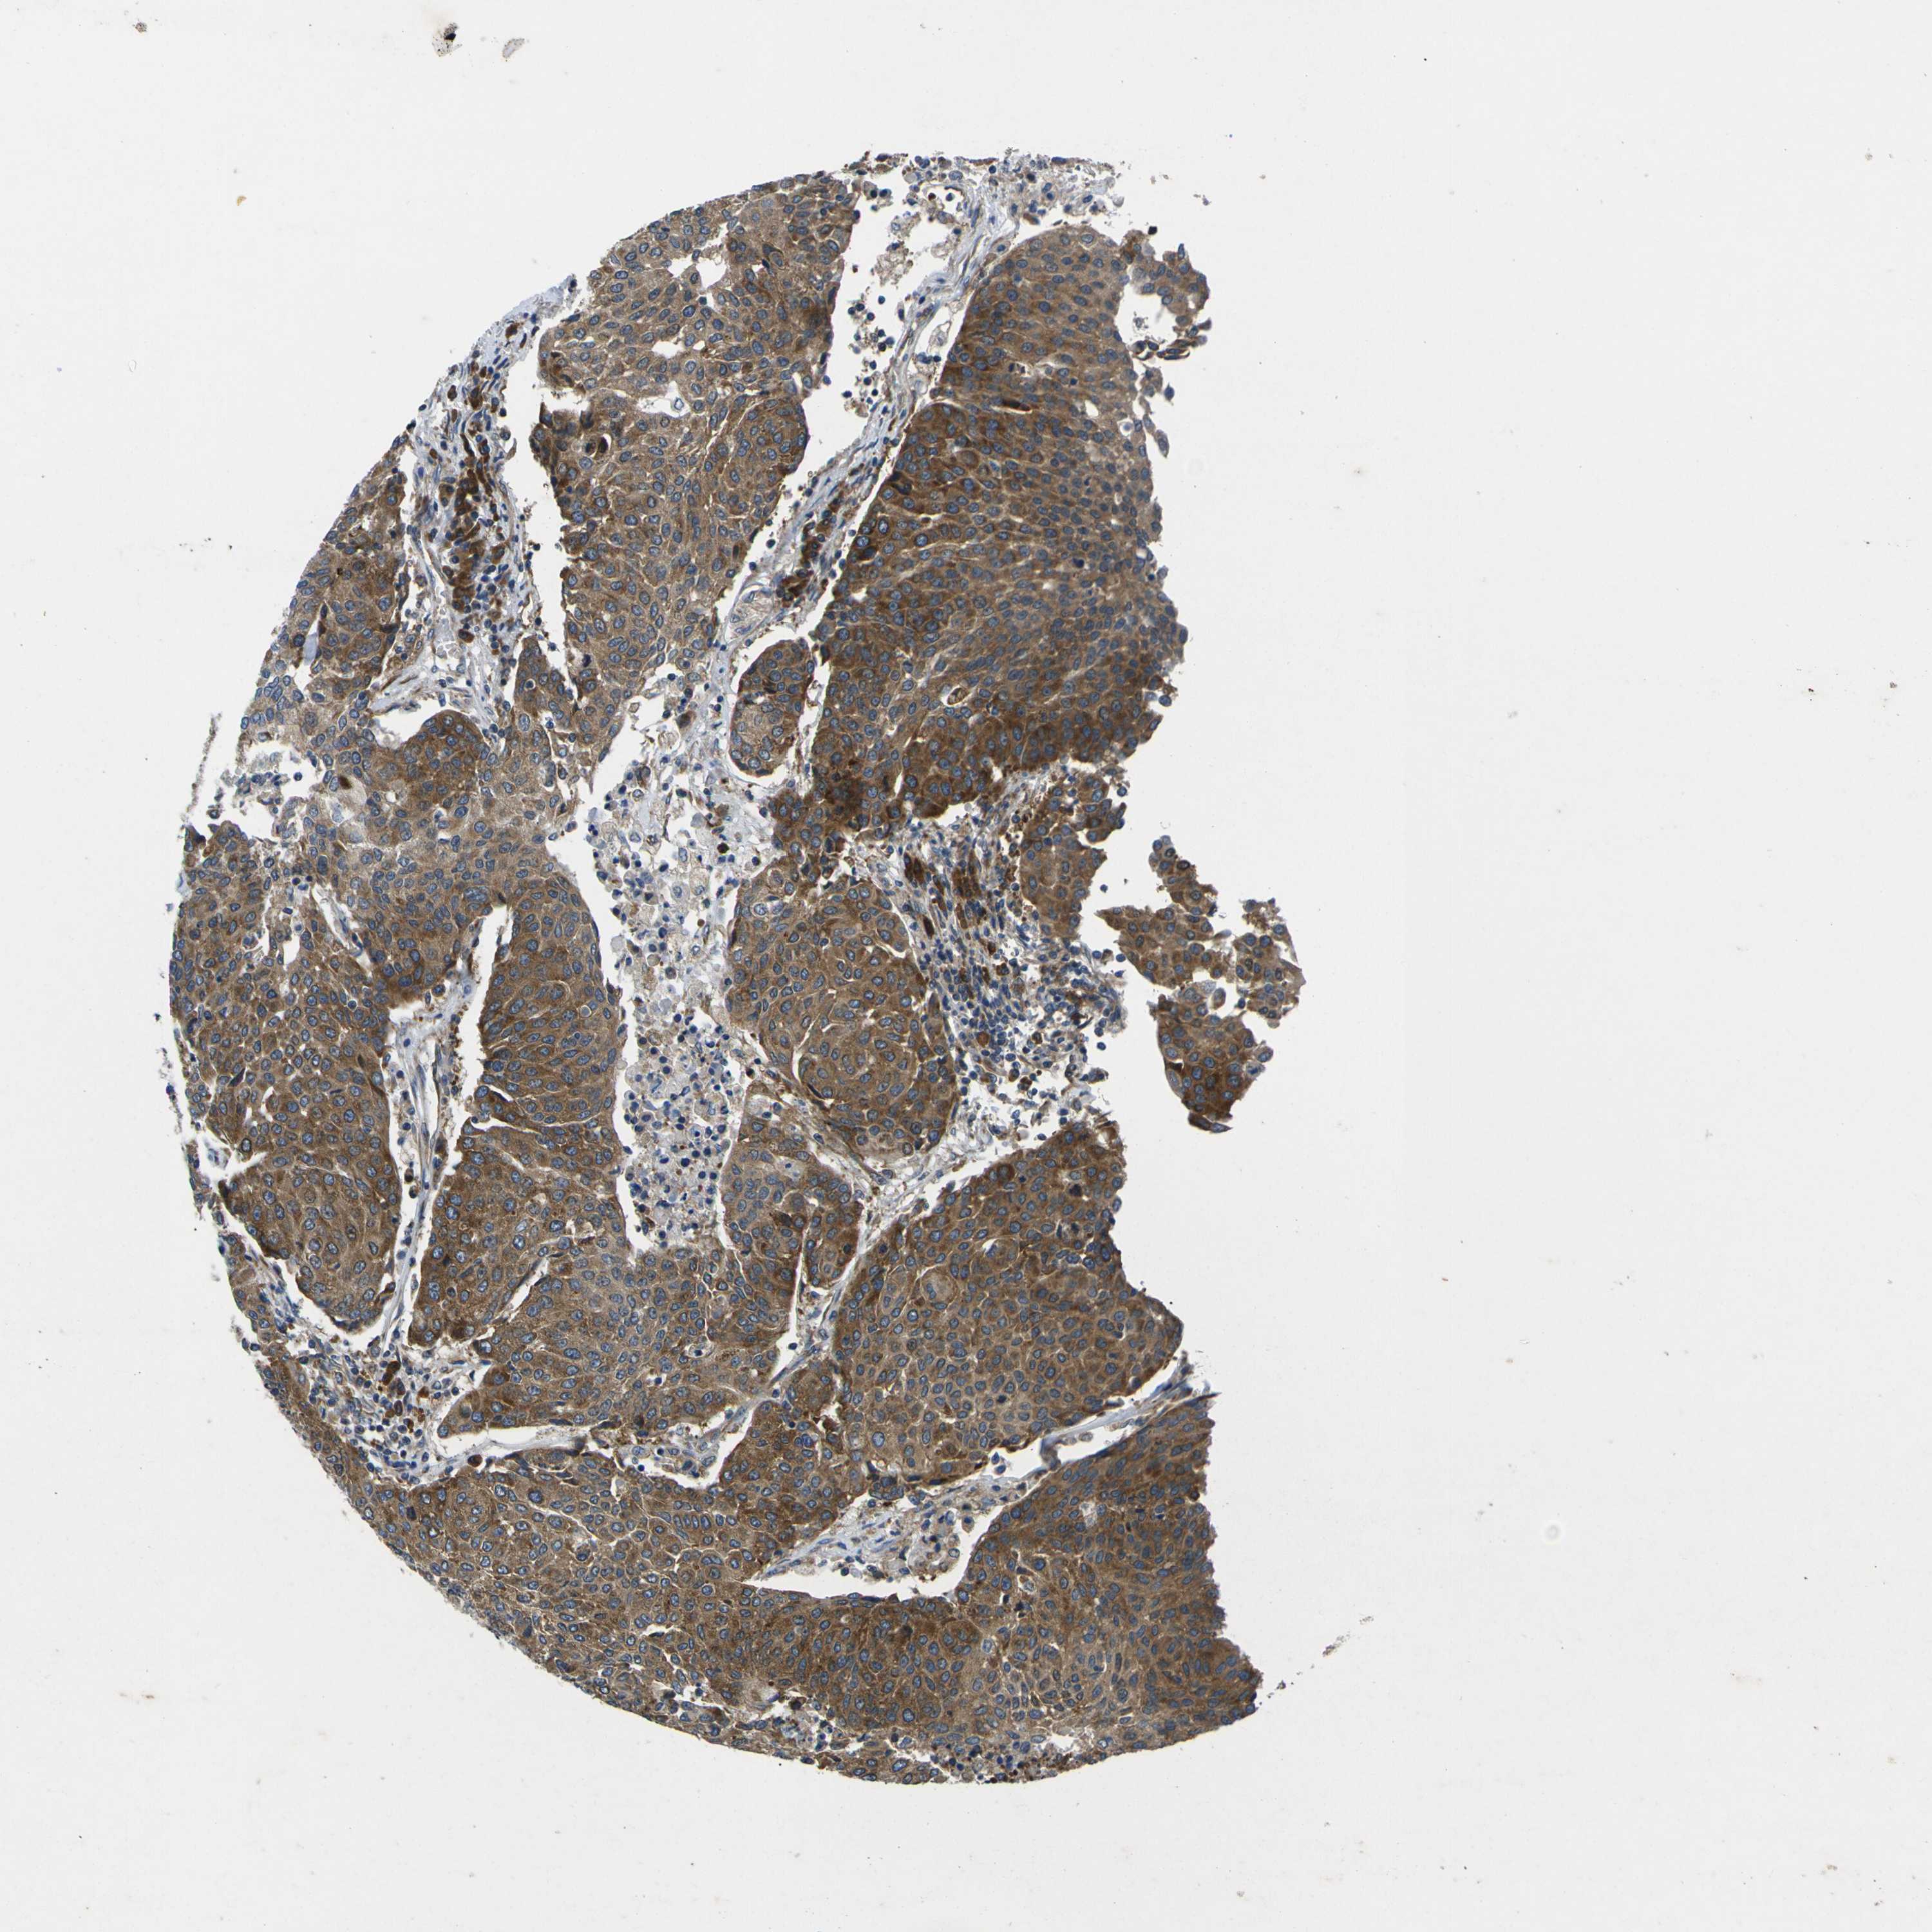

UROTHELIAL CANCER - Protein expressioni

A mouse-over function shows sample information and annotation data. Click on an image to view it in a full screen mode. Samples can be filtered based on level of antibody staining by selecting one or several of the following categories: high, medium, low and not detected. The assay and annotation is described here.

Note that samples used for immunohistochemistry by the Human Protein Atlas do not correspond to samples in the TCGA dataset.

Antibody stainingi

Antibody staining in the annotated cell types in the current human tissue is reported as not detected, low, medium, or high, based on conventional immunohistochemistry profiling in selected tissues. This score is based on the combination of the staining intensity and fraction of stained cells.

Each image is clickable and will lead to virtual microscopy that enables deeper exploration of all samples and also displays staining intensity scores, fraction scores and subcellular localization as well as patient and tissue information for each sample.

Antibody CAB009561

Staining

High

Medium

Low

Not detected

Intensity

Strong

Moderate

Weak

Negative

Quantity

>75%

75%-25%

<25%

None

Location

Nuclear

Cytoplasmic/membranous

Cytoplasmic/membranous,nuclear

Urothelial carcinoma, High grade

Urothelial carcinoma, Low grade